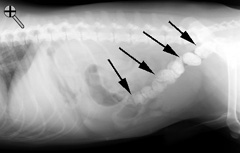

| This animal was NOT properly prepared. Notice the feces in the descending colon. An enema should have been performed prior to the series being started. If you need to review the technique, you can go back to the text describing an upper GI series. Click here to return to the gi series | |